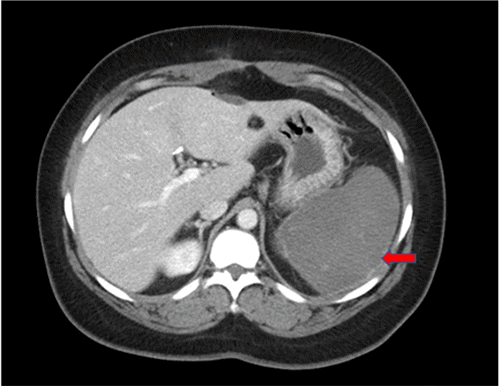

A 47-year-old-female with a past medical history of mitral valve prolapse repair, symptomatic cholelithiasis status post-laparoscopic cholecystectomy with intraoperative cholangiogram and Hb S/β Th presented to the emergency department on postoperative day (POD) 8 with a complaint of left upper quadrant abdominal pain. She reported persistent abdominal pain and constipation since surgery; however, the pain was increasing in severity. A review of systems demonstrated nausea without vomiting. Her vital signs were within normal limits at the time of initial exam, with an oral temperature of 36.9 °C, blood pressure of 112/72 mm Hg, heart rate of 90 bpm, and a body mass index of 32.5 kg/m2. A physical exam of the abdomen revealed a soft abdomen with moderate tenderness to palpation in the epigastric region and left upper quadrant. There was no rigidity, guarding, or peritoneal signs on exam, and the patient was in no acute respiratory distress. The remainder of the physical exam was noncontributory. Laboratory studies revealed an elevated total bilirubin of 1.3 mg/dL (normal range: <1.3mg/dL) and an elevated alkaline phosphatase level of 143 unit/L (normal range: 20-120 unit/L). She was also found to have a white blood cell count of 24,000/cm³ (normal range: 4,500-11,000/cm³) and a platelet count of 582,000/μl (normal range: 150,000-450,000/μl). Her hemoglobin and hematocrit were 9.3 gm/dL (normal female range: 11.6-15.0 gm/dL) and 29.9% (normal female range: 35.5%–44.9%), respectively. Due to her leukocytosis, she received one dose of piperacillin-tazobactam in the emergency department. A contrast-enhanced CT scan of the abdomen demonstrated an acute splenic artery thrombosis originating at the splenic hilum and extending 38 mm proximately toward the celiac trunk and subsequent signs of global splenic infarction (Figure 1). Of note, the patient did not have a history of previous deep vein thrombosis. She received one dose of prophylactic subcutaneous unfractionated heparin (5000 international units) preoperatively in addition to the placement of sequential compression devices (SCD) during the index operation. Given these findings, she was admitted to the general surgery service.

Figure 1. CT of Abdomen with Oral and Intravenous Contrast Showing Splenomegaly, Splenic Artery Thrombosis, and Global Splenic Infarction. Published with Permission